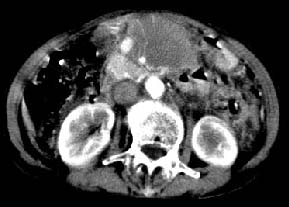

ct:肝胃之间、胰头后、腹主a周围,融合而成团块状影,包绕血管,胰腺前移后缘分界欠清,与肝胃分界清,肿块未见明显强化,肝右叶后段小囊肿。

肝胃之间、胰头后、腹主a周围,融合而成团块状影,包绕血管,胰腺前移后缘分界欠清,与肝胃分界清,肿块未见明显强化,考虑淋巴瘤可能性大

胰腺受压前移,胰管扩张,应为腹膜后占位,病灶密度不均,有低密度坏死区,强化扫描强化不明显腹腔干动脉受侵,考虑腹膜后恶性占位

肝胃之间、肝十二指肠韧带,胰头后、腹主a周围,融合而成团块状影,包绕血管[腹腔干、肠系膜上动脉,腹主动脉],胰腺前移后缘分界欠清,与肝胃分界清,肿块未见明显强化,肝右叶后段小囊肿。

主动脉-胰腺间隙可见巨大分叶状软组织肿块影,包绕腹主动脉、腹腔干及其分支、腔静脉等大血管,增强呈无明显强化,临近脏器明显受压移位,增强示有分界。肝右叶可见局限性低密影,边缘清楚。

影象表现:平扫,首先可见胃壁明显增厚,内外边缘清晰,外缘光滑,内边缘不归整,同时胃腔明显缩小。

再看从肠系膜根部到胰腺后主动脉及上腔静脉周围可见相连的较大的软组织肿块影,形态不规则,呈明显

的大小不等的分叶状,其中密度较均匀但其中可见条状低密度区,肿块边缘比较清晰周围的小肠受压移位

明显且堆积。

增强所见,腹腔动脉,肠系膜上动静脉被肿块包绕,结合平扫的条状低密度区恰好位于血管周围,较大的

肿块强化不明显(遗憾的是没有标上ct值)但胃壁强化的十分明显。